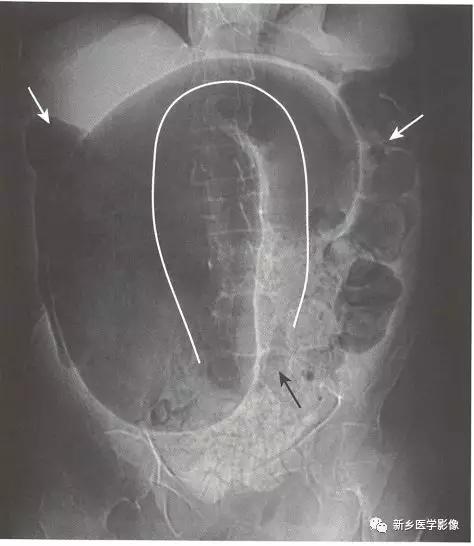

2、机械性小肠梗阻关键的影像学特征

传统X线平片上,梗阻点近端可见多个扩张的小肠肠襻(>2.5cm)。

当肠 腔开始扩张,小肠肠襻逐一 堆积,形成阶梯状外观,一般由左上腹开始,随着疾病进展逐步向右下腹(黑色实线箭头)发展,具体范围及程度取决于小肠梗阻点有多远。

一般来说,若是近端小肠梗阻(例如近端空肠),则扩张的小肠肠襻数量较少;若是远端小肠梗阻(例如回盲瓣处),则扩张的小肠肠襻数量较多。

在直立位或侧卧位片上,在梗阻近端小肠通常可见多个气-液平面。

如果时间足够长,梗阻远端的肠道内容物可完全排出,则在结肠尤其是直肠内只有很少或完全见不到气体影。

在机械性小肠梗阻中,相对于塌陷的大肠,小肠往往表现为不成比例的显著扩张。